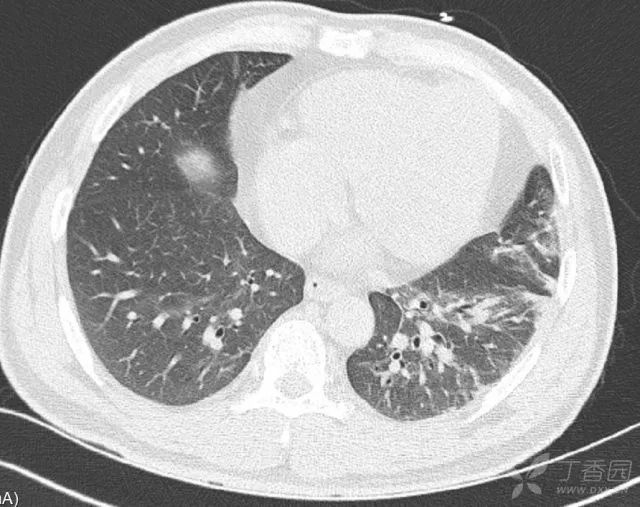

胸部+腹部 CT:两肺炎性病灶,脂肪肝,胰腺尾部稍增粗,双肾周筋膜增厚,少量渗出。双肾低密度灶,左肾结石。阑尾根部稍增粗,升结肠近回盲部肿胀。

患者胸部CT可见两肺炎性病灶,左肺为主